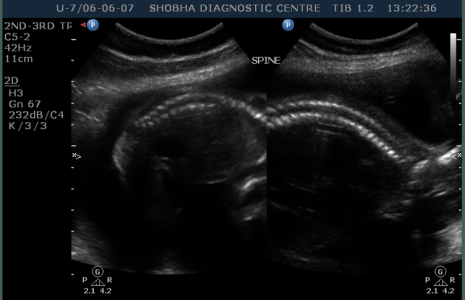

- Thorough scanning of your baby is done to know if baby is developing normally or not. Special attention is paid to brain, face, spine, heart, stomach, bowel, kidneys & limbs.